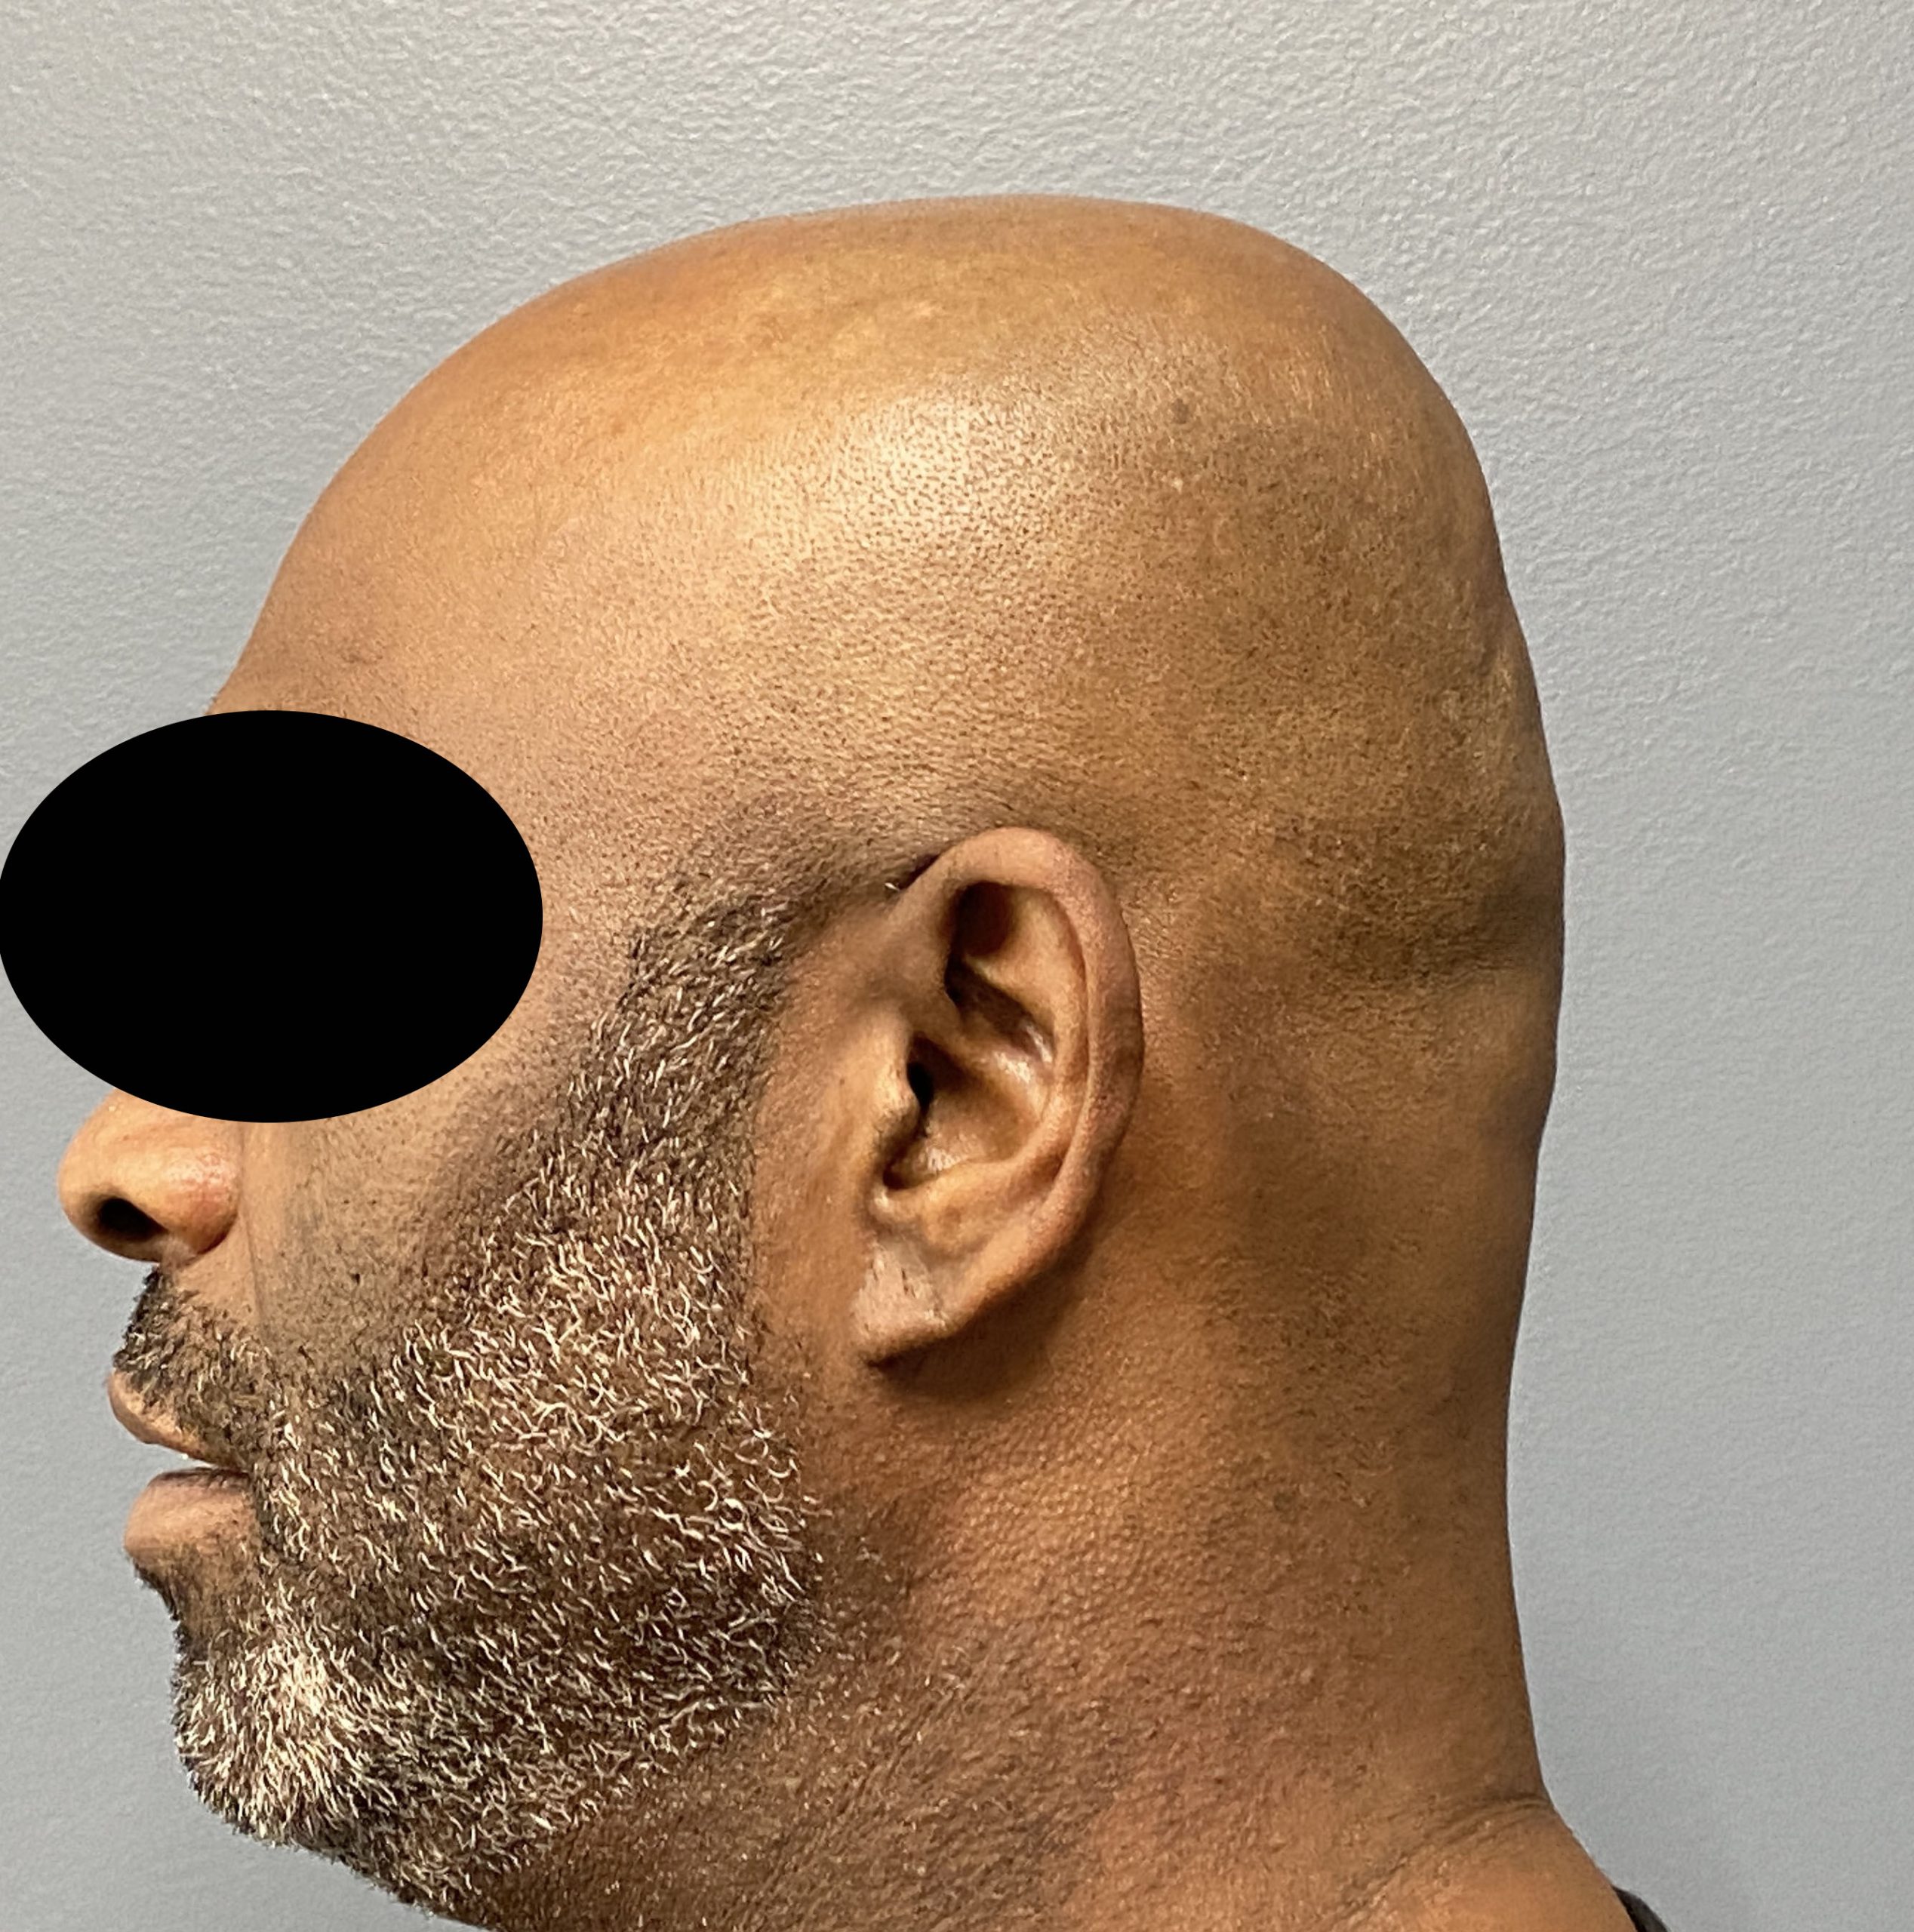

Patient 129

Desire for reduced width/convexity on the sides of his head.

Head narrowing using a temporal muscle transposition technique seen one day postop. He also had an concurrent occipital skull reduction done hence the tape over his incision.

Desire for reduced width/convexity on the sides of his head.

Head narrowing using a temporal muscle transposition technique seen one day postop. He also had an concurrent occipital skull reduction done hence the tape over his incision.